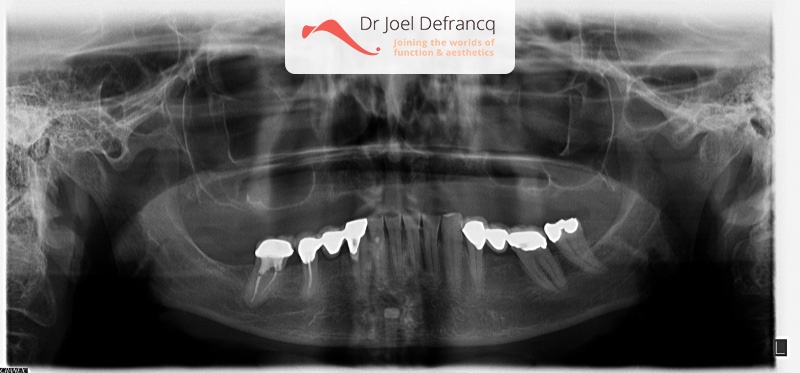

Deze patiënten komen het meest voor. Hun boventanden falen om verschillende redenen: esthetisch, functioneel, cariës, verwaarlozing, parodontitis, infecties allerlei. Zij willen dit proces niet overbruggen met een uitneembare prothese. Bovendien zijn de wangen niet ingevallen, aangezien de bestaande tanden nog altijd ‘volume behoudend’ zijn. Deze patienten zijn dan ook het eenvoudigst te behandelen: